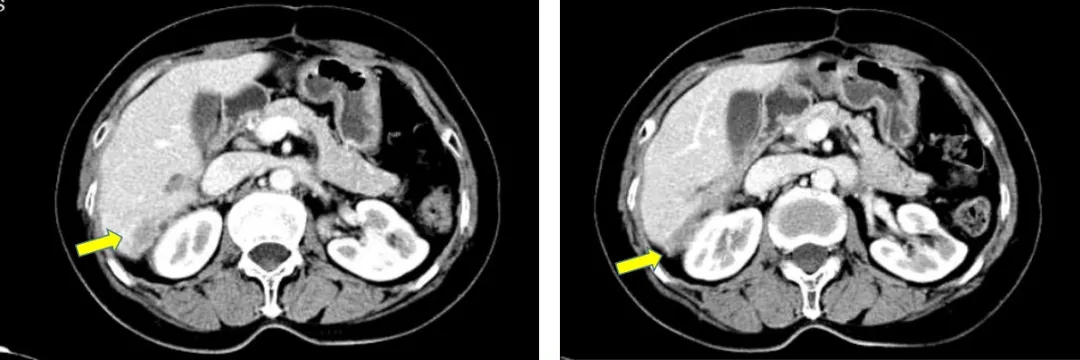

2014.6.11 CT:脾周囊性低密度灶2.4*2.7cm,较2014.2.26增大,腹主动脉旁肿大淋巴结,考虑“卵巢癌复发”。

CT检查结果